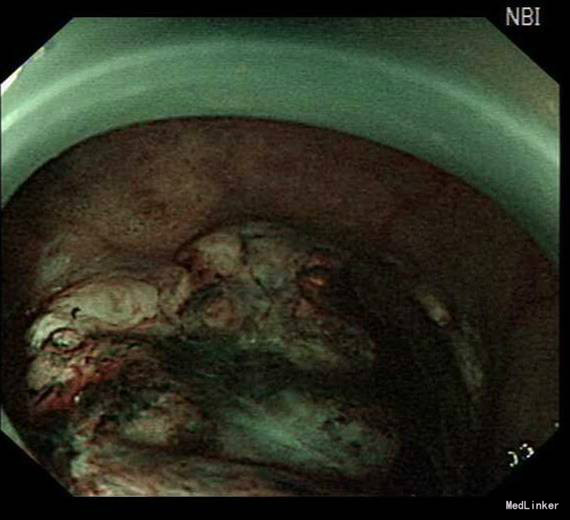

患者,男性,69岁,间歇性中上腹隐痛1月,加剧1周来我院门诊就诊,胃镜检查:见胃窦前壁处可见一1.5*2.0cm粘膜隆起,表面粗糙,见图1,胃镜诊断:胃窦粘膜隆起(性质待病理),慢性浅表性胃窦炎伴胆汁反流,10月26日门诊病理:胃窦:慢性萎缩性胃炎,急性活动,伴部分腺体中重度不典型增生,局灶重度不典型增生。于2015年10月28日入院。

诊疗经过:入院后经过术前检查,行放大内镜检查和超声内镜检查,超声内镜提示:胃窦病灶未突破粘膜下层,诊断考虑:胃早癌。于10月30日行内镜下胃ESD术,术顺,安返病房。经过过制酸、补液等对症处理,3天后患者顺利出院。

随访:出院后2周,电话随访患者,一般情况良好,无不适主诉。 讨论:该患者胃镜见一胃窦前壁粘膜隆起,表面粘膜粗糙,病理示:慢性萎缩性胃炎,伴部分腺体中重度不典型增生,局灶重度不典型增生,超声胃镜病灶未突破粘膜下层,有胃ESD手术指征,故行全麻下胃ESD术。术后病理:胃窦前壁肿瘤:腺上皮高级别上皮同瘤,部分癌变,病变大小1.5*1.1*0.3cm,基底及切缘未见癌。说明手术成功,切缘及基底均无肿瘤侵及。对于早癌患者我们完全可以通过采用ESD方法治愈患者,胃镜下切除早癌较腹腔镜创伤更小。我和患者解释时是这样说的:腹腔镜是微创,而我们内镜下ESD则是微微创。